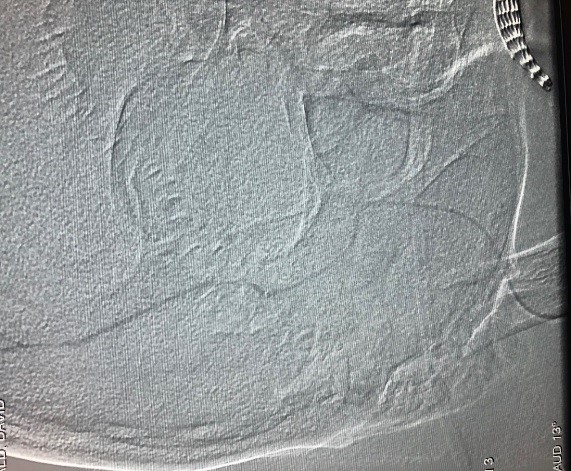

![]() New Imaging | ![]() Previous Imaging |